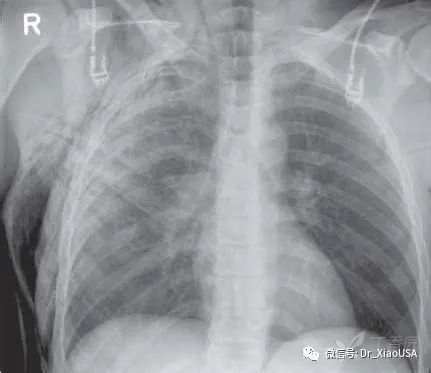

a) 颈部或胸部平片

11.食道破裂典型平片表现是什么?

a) 颈部皮下积气

b) 胸部皮下积气

c) 纵隔气肿